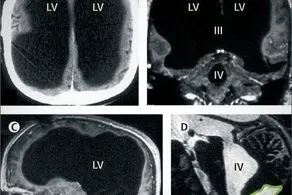

این مرد فرانسوی بعد از احساس ضعف در پای چپ خود و آن هم به مدت دو هفته، به بیمارستان مراجعه کرد. پزشکان بعد از اسکن مغزی او متوجه وجود یک محفظه پر از آب داخل مغزش شدند و به شدت از این قضیه شگفت زده شده بودند.

این اسکن ها نشان می داد که این مرد مغزی در سر خودش ندارد؛ در حالی که مایع مغزی نخاعی به شکل طبیعی در سر او جریان دارد اما از یک قسمت خورده می شود و به دلیل اینکه این مایع وارد سیستم گردش خون او شود، در یک فضای دیگر جای می گیرد. سپس با بررسی های مختلف متوجه شدند که او یک مغز بسیار کوچک در سر خود دارد.

یک فضای سیاه بزرگ با تجمع مایع مغزی نخاعی در مغز این مرد ساخته شده بود. زمانی که این مرد نوزاد بود، یک دستگاه مخصوصی را به سر او وصل کردند و آب اضافه مغزش را بیرون کشیدند و این دستگاه تا سن 14 سالگی به سر او وصل بود تا این که او از ضعف زیاد و نا تعادلی در قسمت پای چپ شکایت کرده و به بیمارستان مراجعه کرد.